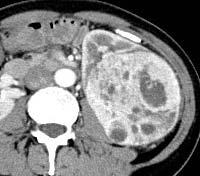

But, when we analyzed the degree of enhancement (hyperdensity, isodensity, hypodensity) in arterial (corticomedullary) and venous (nephrographic) phases showed significant difference. In arterial phase, most of clear cell RCC (21 of 39, 53.8%) showed hyperdensity, whereas none of non -ccRCC (0 of 22,0%) showed hyperdensity. The P value was 0 (P<0.05). In venous phase, ccRCC showed more hyperdensity or isodensity (9 and 4 0f 39, 23.1% and 10.3% respectively) than non-ccRCC (0 and 1 of 22, 0% and 4.5% respectively). Almost all of the non-clear cell RCC ( 21 However, we did not get any significant difference, when compared degree of enhancement in delayed phase (excretory phase). Table 3: shows the comparison of degree of enhancement in different phases in between ccRCC and non-ccRCC. The pattern of enhancement (homogeneous or heterogeneous) showed significant difference. Nonclear cell carcinoma (19 of 22, 86%) showed more heterogeneous enhancement pattern than that of clear cell carcinoma (21 of 39,53%). The P value was 0.012 (p<0.05).

However, when we compared pattern of enhancement, most of clear cell RCC (53.5%) showed heterogeneity, which agree with other studies related with pattern of enhancement of ccRCC [8,10]. But, when we made comparison of heterogeneity in between ccRCC and non-ccRCC, we found that, non-ccRCC were more heterogeneous than ccRCC. This may be because of larger size of non-ccRCC S which tended to show heterogeneity due to propensity of hemorrhage, necrosis and calcification [24][25][26]. At microscopic examination, all tumors with homogeneous enhancement were mainly composed of solid elements, whereas all tumors with heterogeneous enhancement had solid elements, necrosis, hemorrhage and calcifications.

When, we made comparison in between clear cell RCC S and non-clear cell RCC S for the presence of calcification, we found that calcification was significantly more in non-ccRCC (27%) than that of ccRCC S (7%). Calcification suggests a higher 5-years survival rate [3,10].

Calcification is more common in non-clear cell RCC 27% (6 of 22) than clear cell RCC 7% (3 of 39).The p value was significant (p=0.038). In our study, we also made comparison in between non-clear cell RCC and clear cell RCC with hypovascular tumor. We found significant p values when we compared size, location, pattern of enhancement and presence or absence of necrosis in between these two types.